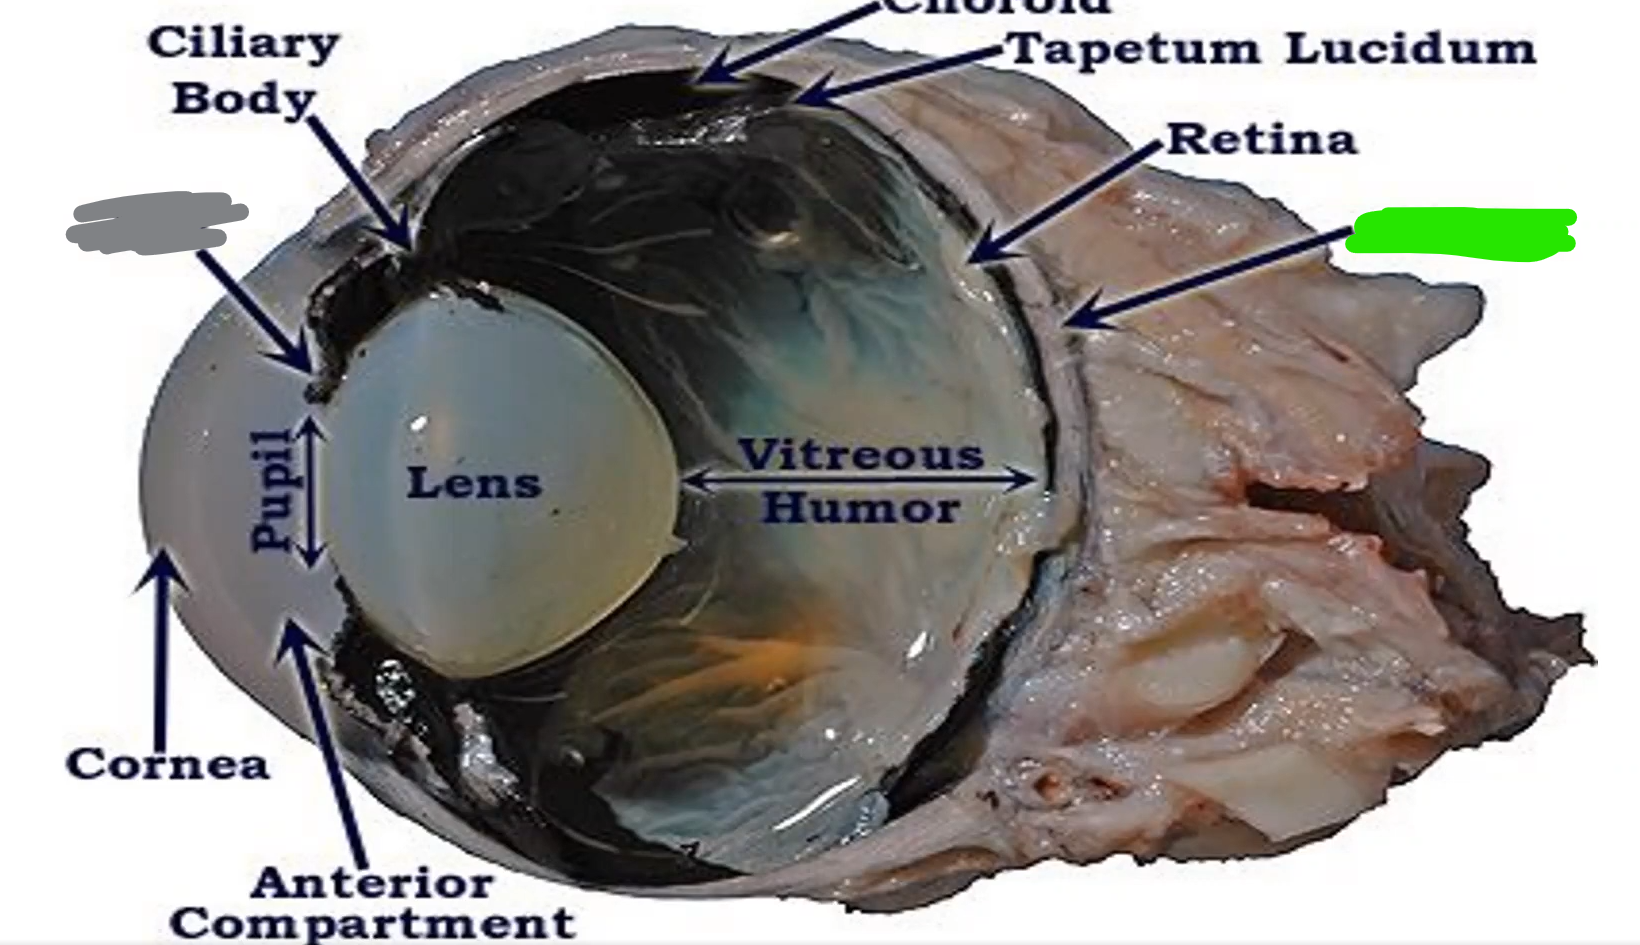

Name

cornea

allows light, most sensitive part of body

Name

Ciliary body

controls shape of lens

Name

Choroid

Name

Tapetum

Name

Optic nerve

Orange name

Retina

Orange

Iris

Blue

Pupil/lens

Red

Lens

Blue

Retina

Green

vitreous humor

Gray

Iris

Green

Sclera

Blue

Pupil

Orange

Anterior compartment

Maintains pressure